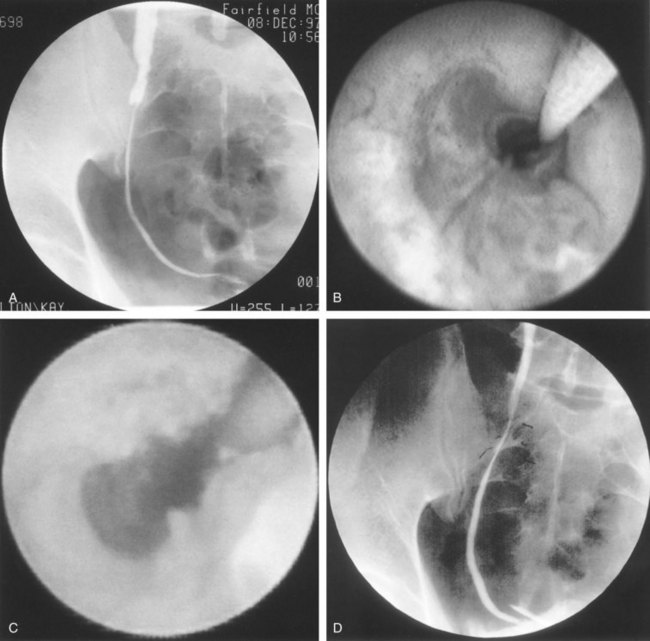

UPJ obstruction, although most often a congenital problem, can present clinically at any time of life. Historically, the most common presentation in neonates and infants was the finding of a palpable flank mass. However, the current widespread use of maternal, prenatal ultrasonography has led to a dramatic increase in the number of asymptomatic newborns being diagnosed with hydronephrosis, many of whom are subsequently found to have UPJ obstruction (Bernstein et al, 1988; Wolpert et al, 1989). A fraction of cases may also be found during evaluation of azotemia, which may result from bilateral obstruction in a functionally or anatomically solitary kidney. UPJ obstruction may also be incidentally found during studies performed to evaluate unrelated anomalies such as congenital heart disease (Roth and Gonzales, 1983). In older children or adults, intermittent abdominal or flank pain, at times associated with nausea or vomiting, is a frequent presenting symptom. Hematuria, either spontaneous or associated with otherwise relatively minor trauma, may also be an initial symptom. Laboratory findings of microhematuria, pyuria, or frank urinary tract infection might also bring an otherwise asymptomatic patient to the urologist. Rarely, hypertension may be a presenting finding (Riehle and Vaughan, 1981). Radiographic studies should be performed with a goal of determining both the anatomic site and the functional significance of an apparent obstruction. Although excretory urography remains a reasonable option for radiographic diagnosis, this study is less commonly used today. Classically, excretory urographic findings include delay in function associated with a dilated pelvicalyceal system. If the ureter is visualized, it should be of normal caliber. In some patients, symptoms may be intermittent and urography between painful episodes may be normal. In such cases the study should be repeated during an acute episode when the patient is symptomatic (Nesbit, 1956). Provocative testing with diuretic urography may allow accurate diagnosis in select cases. The patient should be well hydrated and the study then performed after injecting furosemide, 0.3 to 0.5 mg/kg (Malek, 1983) (Fig. 41–2).

Figure 41–2 A, This patient with intermittent left flank pain underwent intravenous urography. The calyces are sharp bilaterally without evidence of obstruction. However, there is a “box-shaped” pelvis on the left side, which may be associated with intermittent obstruction. B, This intravenous urogram in the same patient was performed along with injection of intravenous furosemide, which brought out the obvious left-sided ureteropelvic junction obstruction. The patient’s symptoms were subsequently relieved with a left pyeloplasty.

CT scan is frequently obtained for any patient presenting with acute flank pain (Fielding et al, 1997; Dalrymple et al, 1998; Vieweg et al, 1998) (Fig. 41–3). Moreover, CT scans provide detailed anatomic and functional information to aid in diagnosis of UPJ obstruction (Fig. 41–4A-C). Both ultrasonography and CT scanning also have a role in differentiating acquired causes of obstruction such as radiolucent calculi or urothelial tumors. In neonates and infants, the diagnosis of UPJ obstruction has generally been suggested either by routine performance of maternal ultrasonography or by the finding of a flank mass. In either setting, renal ultrasonography is usually the first radiographic study performed. Ideally, ultrasonography should be able to visualize dilatation of the collecting system to help differentiate UPJ obstruction from multicystic kidney and determine the level of obstruction. UPJ obstruction and multicystic kidneys are distinguishable in the majority of cases by ultrasound alone. With UPJ obstruction, the pelvis is visualized as a large, medial sonolucent area surrounded by smaller, rounded sonolucent structures representing dilated calyces. At times, dilated calyces will be seen connecting to the pelvis via dilated infundibula (Fig. 41–5).

Figure 41–4 A, Contrast-enhanced CT scan identifies a classic ureteropelvic junction (UPJ) appearance in early-phase imaging. B, Early images reveal normal nephrogram and delayed filling of the obstructed, dilated UPJ. C, Delayed images demonstrate holdup of contrast drainage on the right compared with the normal left side.